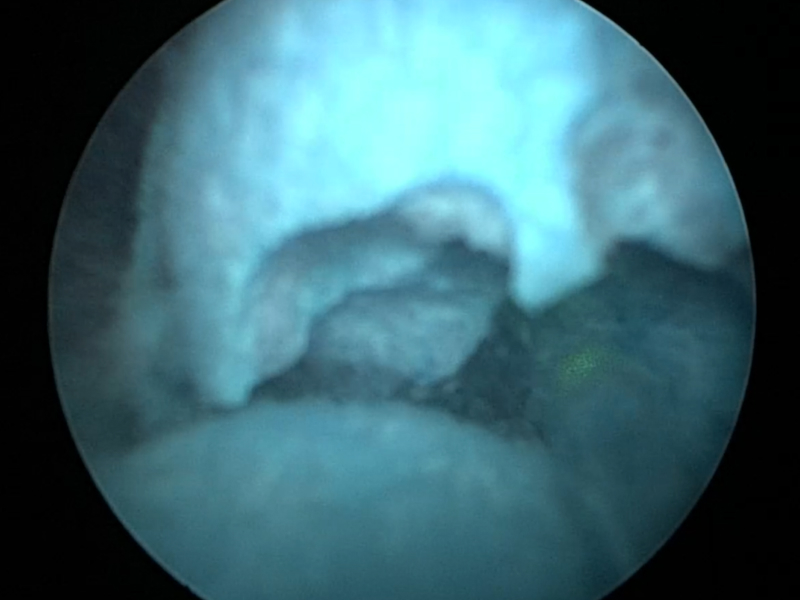

It’s Advanced! 경피적 신장결석 제거술,

골드만이 앞서가는 이유 BIG 5

전날 입원, 전신마취, 긴 회복 기간? 골드만에서는 모두 NO!

환자 중심으로 설계된 새로운 PCNL 시스템을 경험하세요.